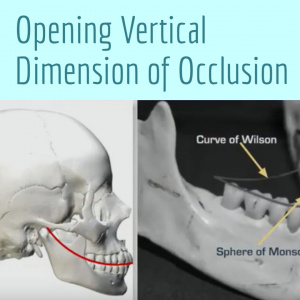

Opening Vertical Dimension of OcclusionOpening Vertical Dimension of Occlusion (and Adjunctive Occlusal Procedures) Gordon J. Christensen, DDS, MSD, PhD Occlusion is one of the most controversial and frustrating areas of dentistry, yet y...... |